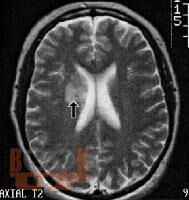

Неврологические осложнения системной красной волчанки

Учебное пособие содержит информацию о вариантах поражения нервной системы у лиц, болеющих системной красной волчанкой. Данное пособие предназначено для неврологов, врачей общей практики, педиатров, терапевтов, ревматологов